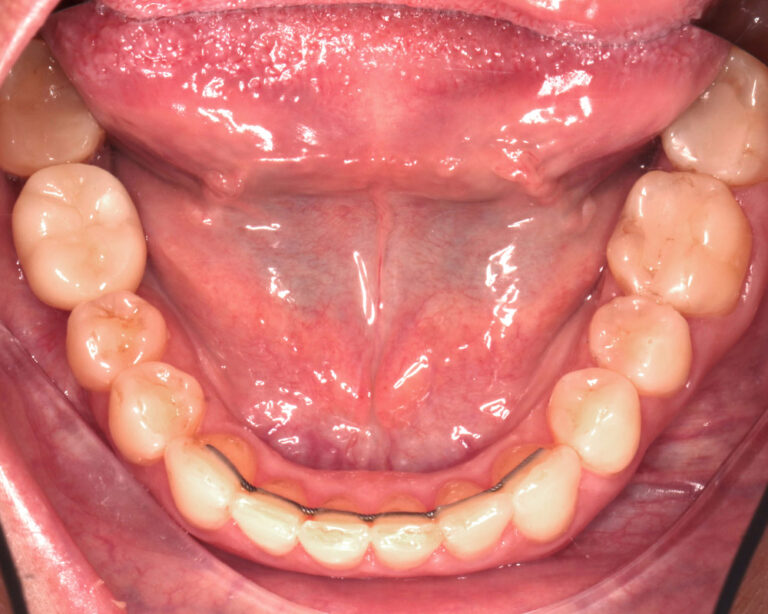

Кейс 21

Юрченко Павел Николаевич

Количество кап ВЧ 32

Количество кап НЧ 32

ДО

ПОСЛЕ